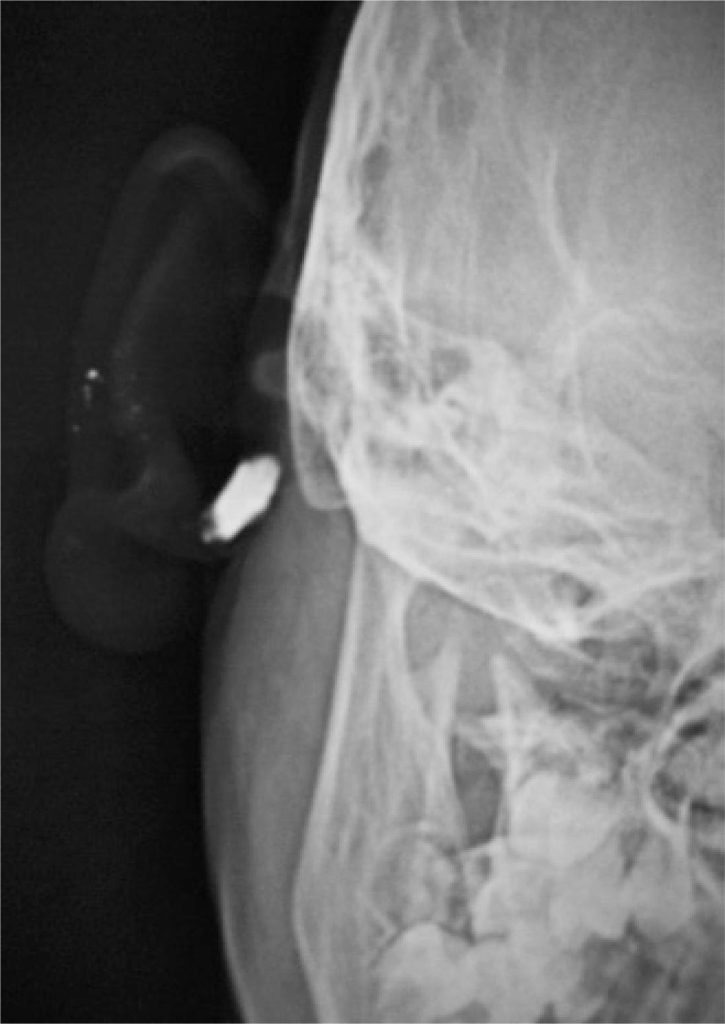

Menina de 8 anos com queixa de saída de secreção intermitente de um orifício situado na face medial do pavilhão auricular direito desde a tenra infância. A secreção era em pequena quantidade, com mal odor, aspecto mucoide e ocasionalmente purulenta. Aumentou a frequência no último ano, com o desenvolvimento um inchaço, logo abaixo do orifício, que inflamou muitas vezes e causou dor. Ao exame, observou-se uma abertura bem acima lóbulo, em direção a um edema que chegava ao sulco pós-auricular (). Uma área de cicatrização e pigmentação na face lateral do pavilhão auricular, imediatamente próxima ao conduto auditivo externo (CAE) − remanescente de inflamações prévias envolvendo a pele do CAE, foi observada e correspondia à fístula (). Outros orifícios semelhantes e assintomáticas foram vistas na hélix ascendente do pavilhão auricular direito () e esquerdo (). Após controlar a infecção com antibióticos, um raio X de seios da face foi solicitado para avaliar a lesão pós-auricular, o qual mostrou uma fístula em formato de balão no tecido mole de todo pescoço, logo abaixo do processo mastoide e do CAE, e posterior ao ramo da mandíbula (). A fístula foi operada sob anestesia geral. Na cirurgia, observou-se que a fístula tinha fundo cego e terminava pouco antes de invadir o tecido da parótida